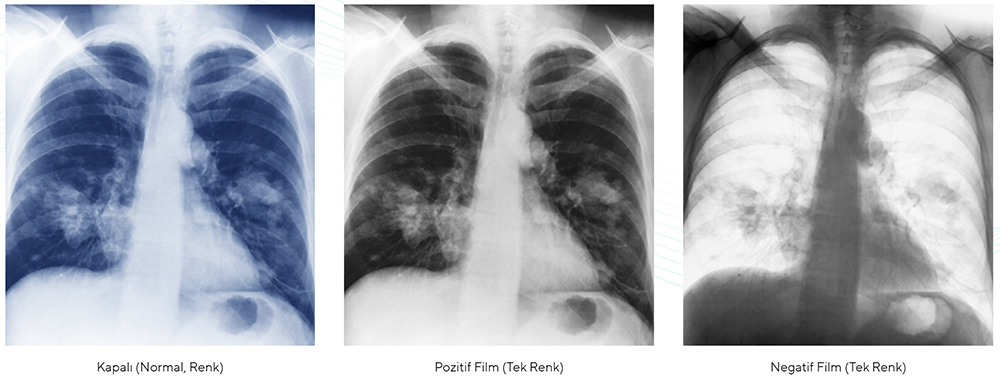

değişebilir renk ve tek renk görüntü

asus healthcare ekranlar, farklı derinliklerden röntgen okumaya yardımcı olmak için iki pozitif ve negatif film moduna sahip renkli ve tek renkli kullanım modlarına sahiptir.